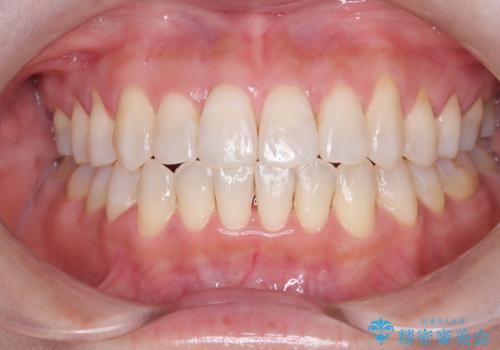

[ インビザライン ] 目立たないマウスピース矯正で、前歯のがたつきをきれいにしたい

担当医 大元洋佑

![[ インビザライン ] 目立たないマウスピース矯正で、前歯のがたつきをきれいにしたいの症例 治療前](https://seimitsushinbi.jp/wp/wp-content/uploads/2024/04/IMG_3912-500x350.jpg?v=1711960039)

![[ インビザライン ] 目立たないマウスピース矯正で、前歯のがたつきをきれいにしたいの症例 治療後](https://seimitsushinbi.jp/wp/wp-content/uploads/2024/04/cd64e6566cc0683feee2abf20f8241f9-500x350.jpg?v=1711960118)